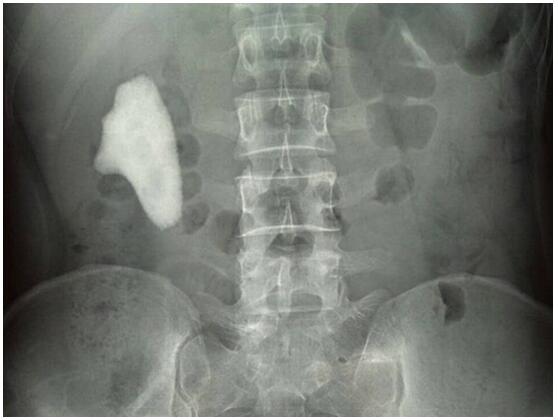

周先生的X光片,可以清楚地看到结石几乎占满整个肾脏。

“右肾内见一巨大高密度阴影,大小约7.7×4.7cm。”原自治区人民医院放射科主任、南宁博锐(结石病)医院放射科专家吴大哲教授表示,通过X线检查,可以清楚看到周先生体内结石十分巨大,并出现右肾下垂(下极达到髂窝)。另外,通过CT检查,也发现右肾盂输尿管移行处有大小约50×25×58mm结石影,右肾盂、右输尿管上段积水扩张。

“这块石头几乎占满整个肾脏,如果不及时取出,会进一步影响肾功能。”苏小壮主任建议通过手术取出,同时采取右肾盂矫形术、右肾固定术来解决患者右肾下垂的问题。